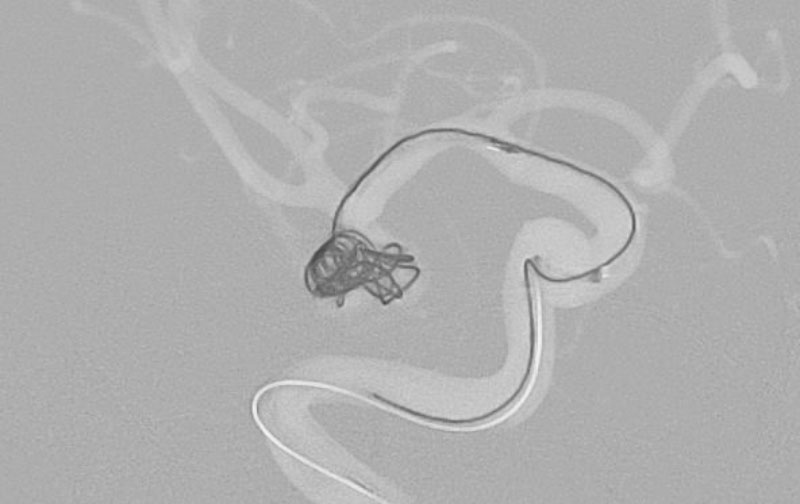

No.1600 手術中